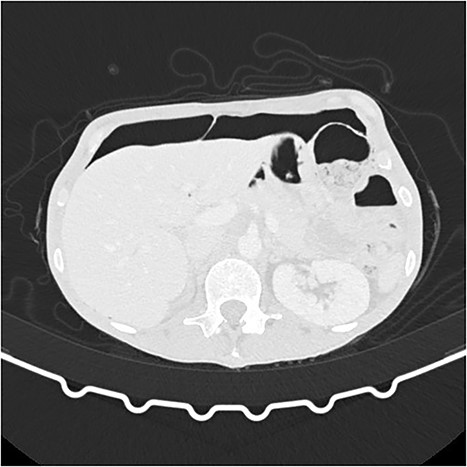

A 55-year-old woman was being followed in a gynecology consultation for a large abdominal mass, likely of adnexal origin (370 mm in its largest dimension). She underwent a hysterectomy, bilateral adnexectomy, and segmental enterectomy due to an iatrogenic perforation of a small bowel loop. On the seventh postoperative day, due to the absence of intestinal transit since surgery, an abdominal X-ray was requested, and general surgery was consulted, suspecting pneumoperitoneum. In this context, the patient underwent a CT scan, which revealed “pneumoperitoneum in the free cavity, significant for one week postoperative, with about 4 cm anteroposterior diameter in the epigastric region. There is also a significant amount of retroperitoneal air in the left pelvic cavity, extending to the presacral space. There are no gas bubbles immediately adjacent to the surgical suture lines.” (Figs 3 and 4). Blood tests showed no significant alterations, and clinically, the patient was hemodynamically stable with only mild tenderness on abdominal palpation, without guarding. Based on the clinical, laboratory, and imaging findings, it was decided to keep the patient on a nil-by-mouth diet with clinical observation. The next day, the patient resumed intestinal transit, allowing for the reintroduction of an oral diet. Blood tests showed no increase in inflammatory markers. The patient continued to progress favorably during the remainder of her hospital stay and was discharged on the tenth postoperative day.